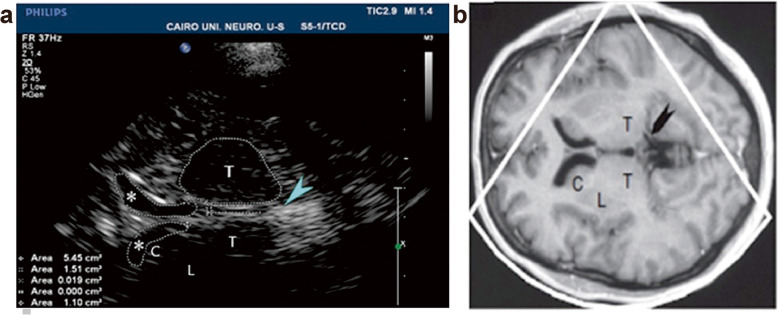

Methods: This study enrolled 26 patients with IGE and 26 age- and sex-matched controls. All participants underwent comprehensive evaluations including clinical examination, electroencephalography, magnetic resonance imaging epilepsy protocol, transcranial sonography (TCS) for third and lateral ventricular diameter measurements, and cognitive assessment using the Addenbrooke's Cognitive Examination-III (ACE III).

Results: This study found significantly lower scores in attention, memory, fluency, and total score of ACE-III in IGE patients compared to the control group (P-value = 0.011, 0.033, 0.007, and 0.001, respectively). However, no significant differences were observed between IGE patients and the control group in language and visuospatial score (P = 0.479 and 0.108, respectively). The average diameters of the third ventricle and lateral ventricle anterior horns were significantly larger in patients than in the control group (P-value 0.004, 0.009, and 0.012, respectively).

Conclusions: IGE patients exhibit significant cognitive impairment and notable dilatation of the third ventricle and lateral ventricles horns, which may serve as markers of brain atrophy.